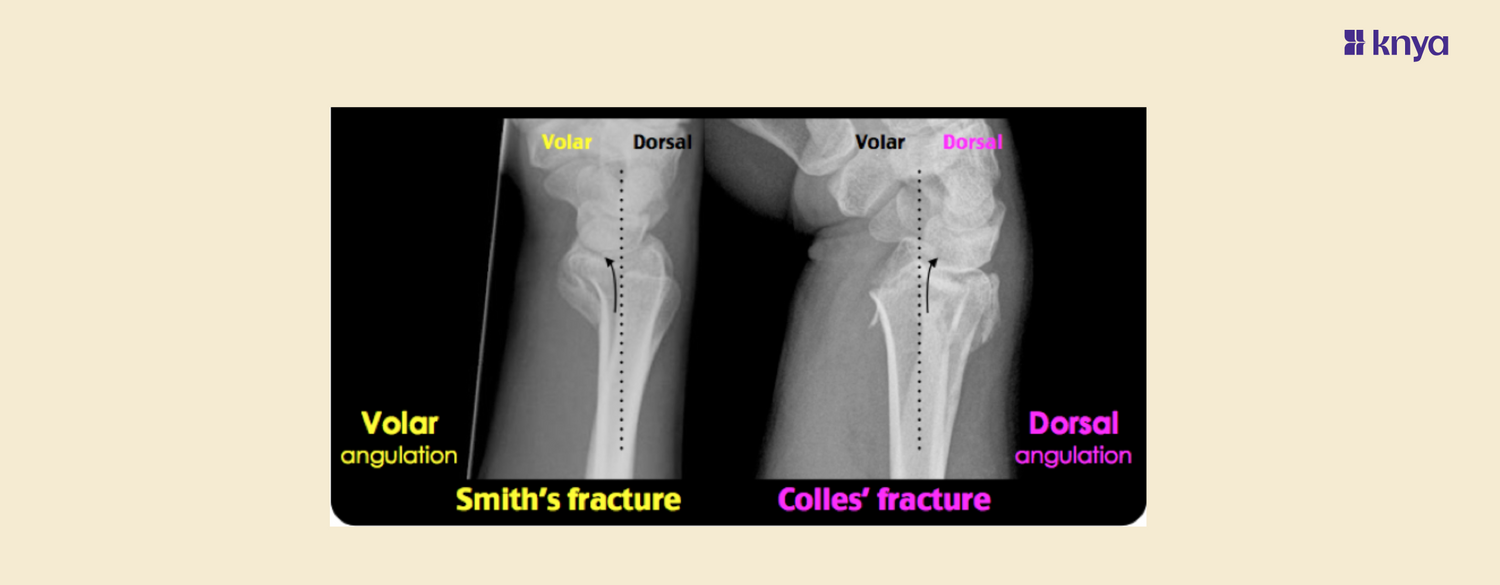

| Radiographic Appearance | Dorsal angulation, radial shortening | Volar angulation, no radial shortening |

A Colles fracture, named after Abraham Colles who first described it in 1814, is one of the most common fractures of the distal radius. It typically occurs when a person falls onto an outstretched hand (FOOSH) with the wrist in extension. The hallmark of a Colles fracture is the dorsal displacement of the distal fracture fragment.

Smith Fracture is a type of broken wrist, or fracture of the distal radius, that occurs when the wrist is bent or flexed during a fall or other trauma. This forces the wrist into flexion, causing the distal fragment to displace volarly. This is also known as a reverse Colles fracture, involving a volar displacement of the wrist and hand.

Similar to Colles fractures, diagnosis is made through physical examination and confirmed by X-rays, which show the volar displacement of the distal fragment.